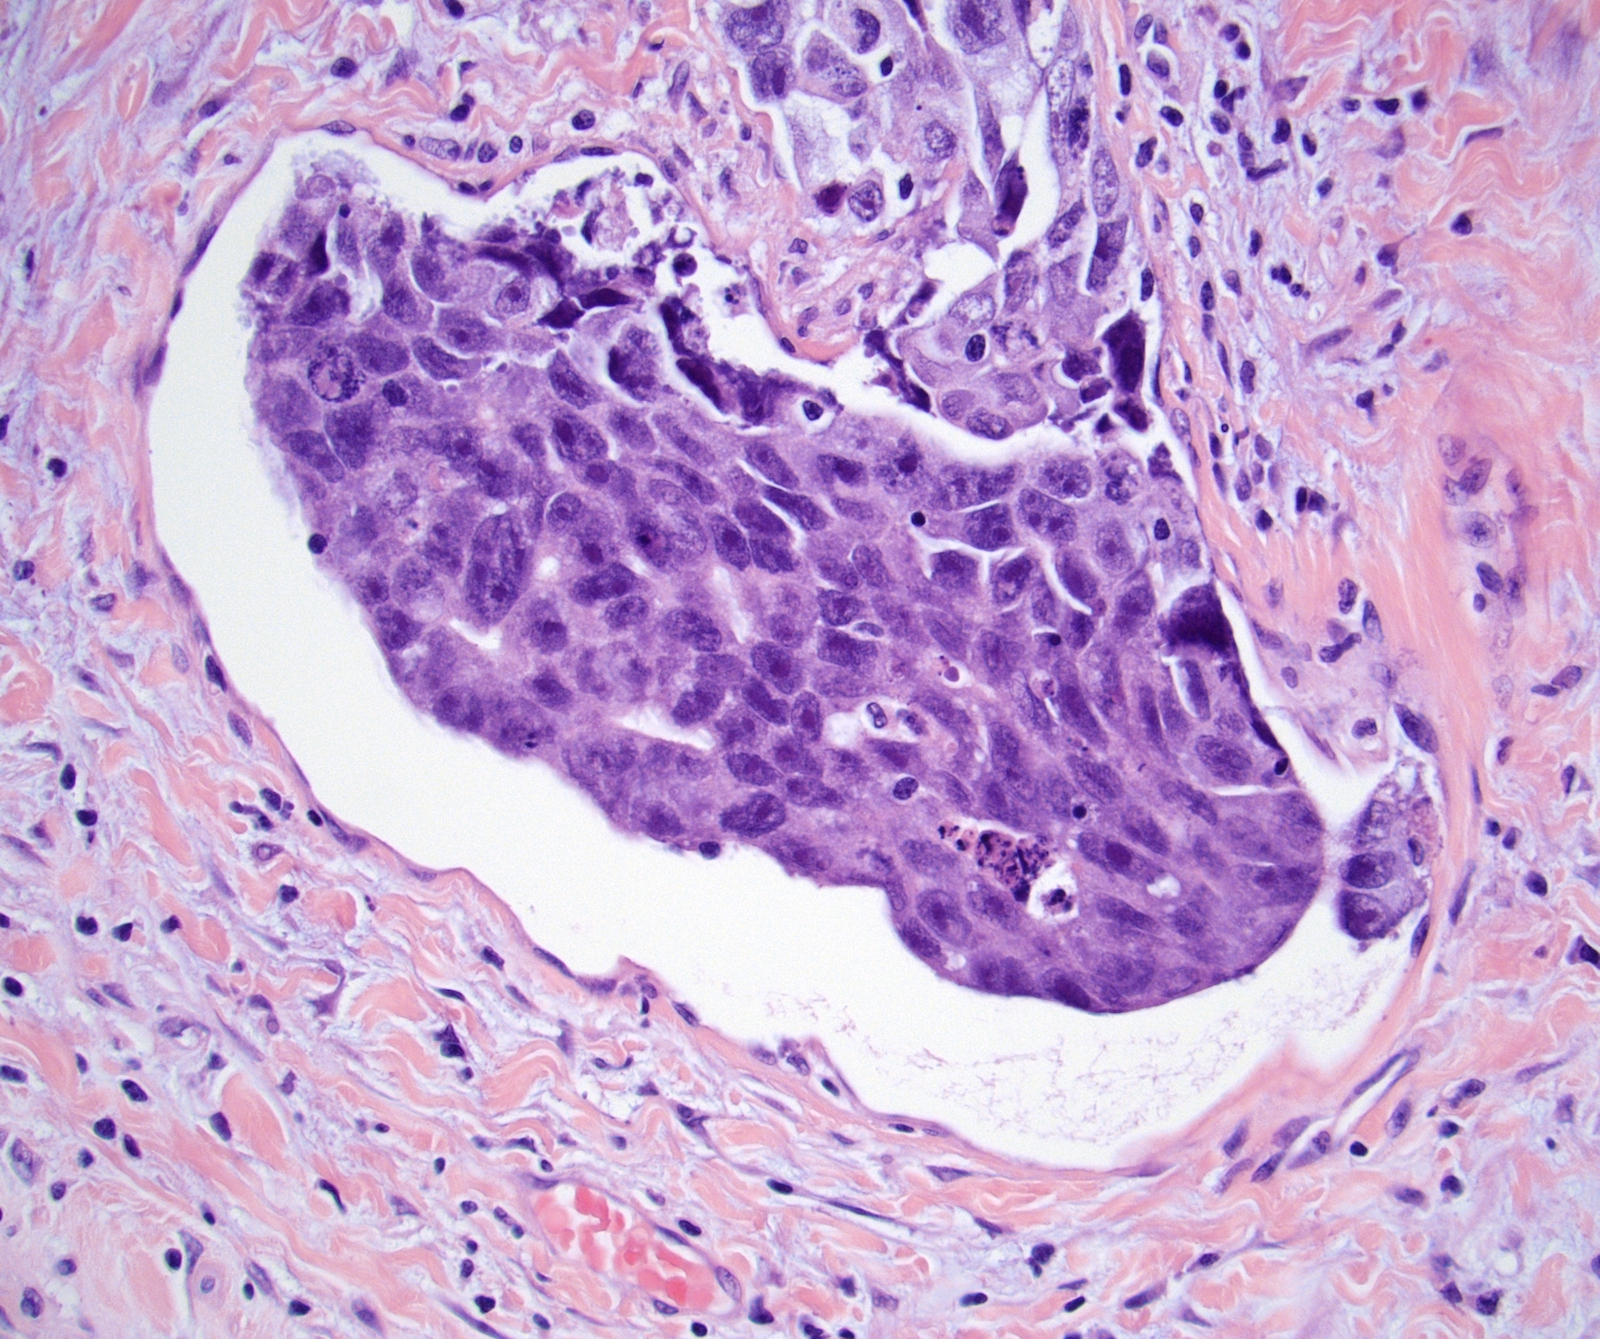

Microscopic (histologic) images

Board review style question #1

In a postpubertal testicular germ cell tumor, lymphovascular (shown above), hilar fat, epididymal and tunica vaginalis invasion are all a part of which pT category?

Board review style answer #1

D. pT2. Lymphovascular, hilar fat, epididymal and tunica vaginalis invasion are all a part of the pT2 category for testicular germ cell tumors. Lymphovascular invasion by embryonal carcinoma is shown in the image.

Comment Here Reference: